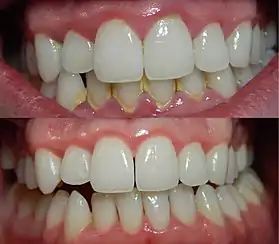

العلاج

محور العلاج هو إزالة البلاك.[13] ويهدف العلاج إلى الحد من بكتيريا الفم، ويمكن أن يأخذ شكل زيارات دورية منتظمة إلى طبيب الأسنان بالإضافة إلى الاهتمام بـالرعاية الصحية المناسبة للفم. يمكن استخدام العديد من الطرق المستخدمة في الوقاية من التهاب اللثة لعلاج التهاب اللثة الواضح مثل:

- تقليح الأسنان وكشط الجذر

- كشط الأنسجة

- استخدام غسول للفم المحتوي على الكلورهيكسيدين أو بيروكسيد الهيدروجين.

وجدت الأبحاث ان المكونات النشطة التي تقلل البلاك وتثبت فعالية الحد من التهاب اللثة على مدى فترة من الزمن" هي مادة التراي كلوسان (triclosan digluconate) , الكلورهيكسيدين، ومزيج من الثيمول، المنثول، eucalyptol ، و أحماض الميثيل ساليسيلات salicylate.

- استخدام الفرشاة، وتعتبر النوع المذبذب الأفضل، بالإضافة إلى استخدام الخيط السني أو الفرش اللثوية / جهاز ري الفم والذي يعمل على تنظيف ما بين الاسنان .[4][12]

في حالة المسببات الأخرى، يجب مراجعة الطبيب للتشخيص، وأحيانا يحتاج لتدخل الجراحي أو العلاج بالأدوية. من الممكن علاج اللثة التام من الالتهابات، في كل الحالات تقريبا، وذلك بواسطة مراقبة ومعالجة طبقة الجراثيم التي تتراكم على الأسنان. العلاج السليم لطبقة الجراثيم يشمل التنظيف المهني لدى اختصاصي، مرتين كل سنة، إضافة إلى استعمال النصاح السني والحرص على تنظيف الأسنان بواسطة الفرشاة بشكل يومي.[14]